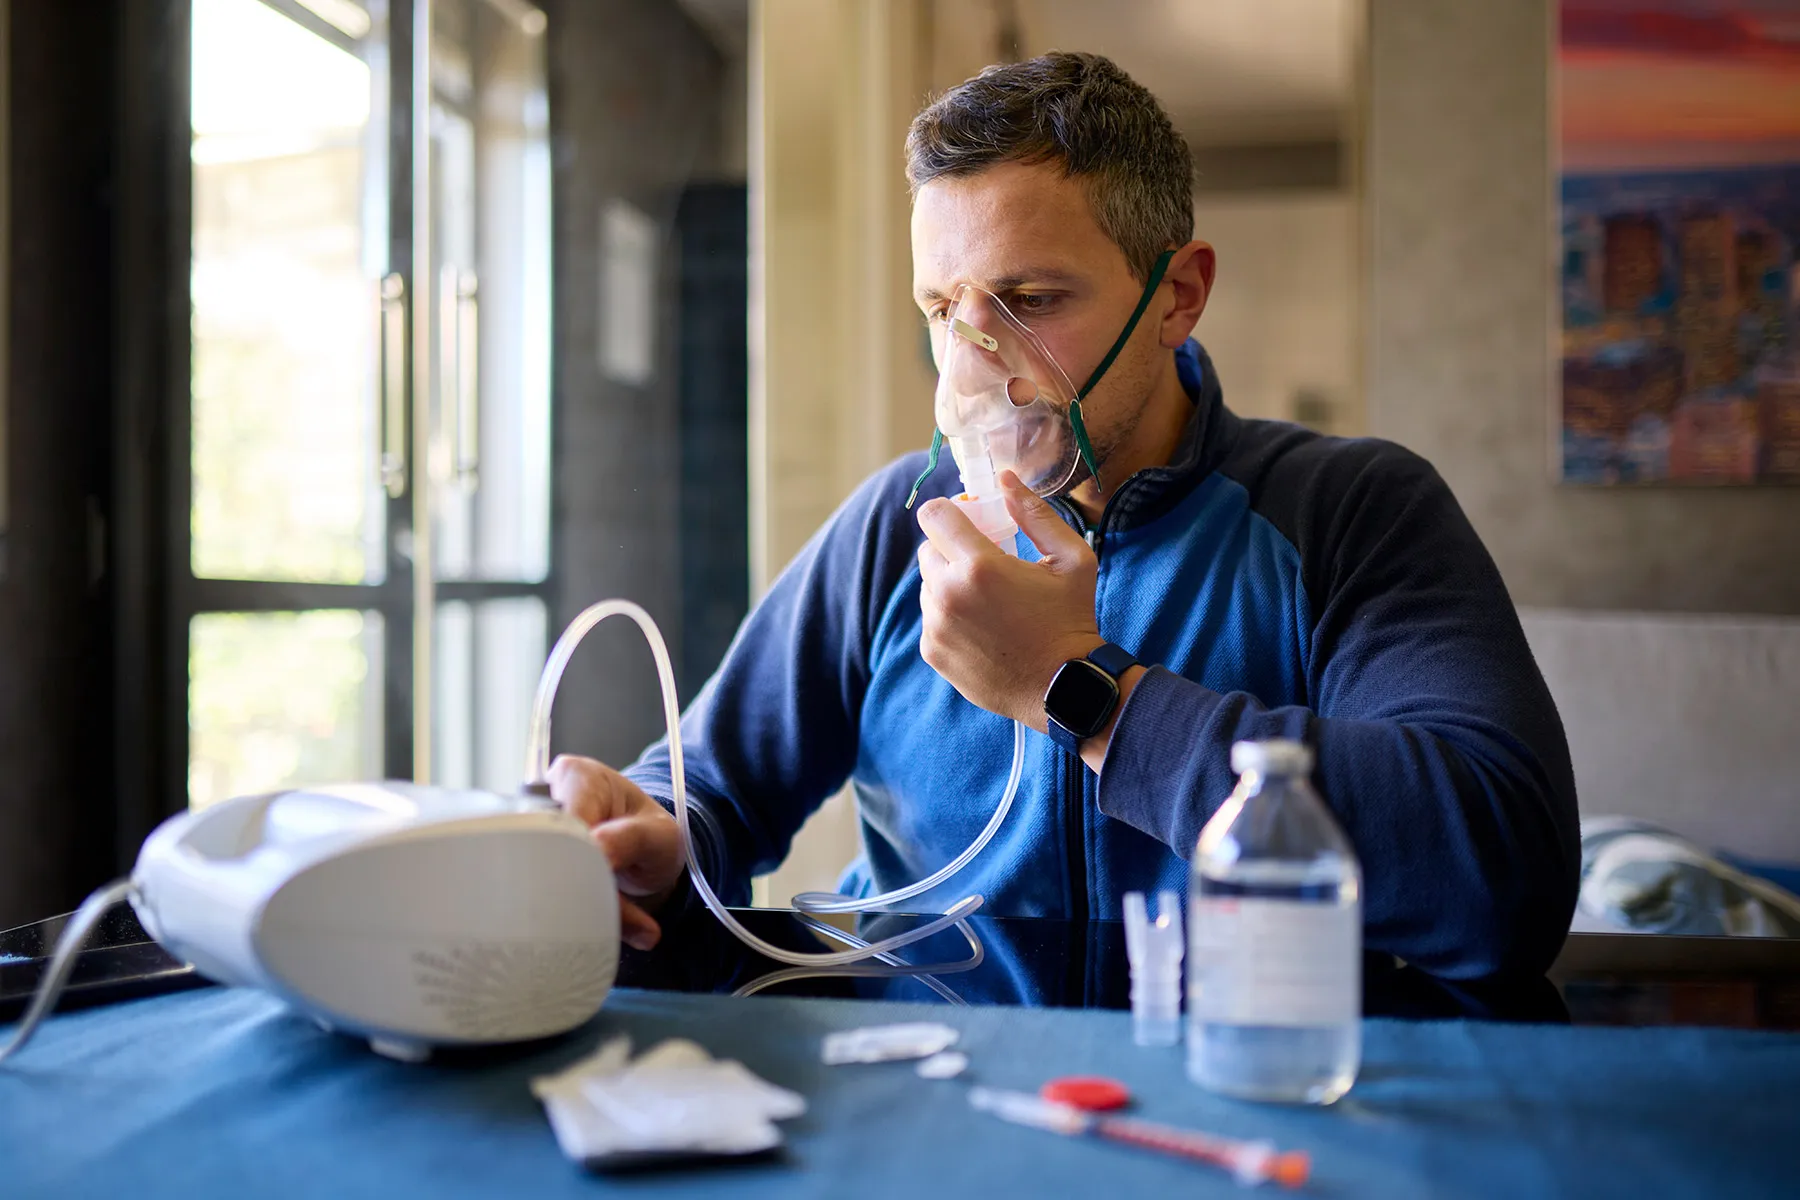

Advanced management of chronic obstructive lung disease — inhalers, rehab, and oxygen therapy.

Targeted antibiotic therapy and follow-up care for community and hospital-acquired infections.

Home and lab-based sleep studies followed by CPAP titration and lifestyle counselling.